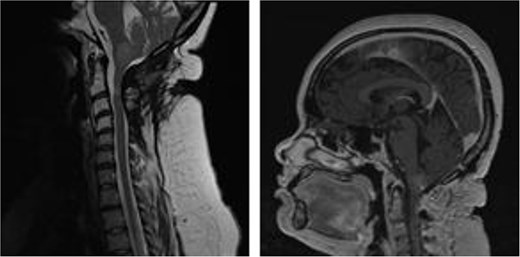

A scheduled suboccipital craniotomy, C1 laminectomy and C2–C4 laminoplasty, was performed. Intra-operatively two distinct, separate lesions were identified. An extra-axial tumor and an intrinsic cerebellar mass with invasion into the underlying brainstem was noted (Fig. 2). There were clear pial margins between both lesions. Gross total resection was achieved for the extra-axial mass and a subtotal resection was achieved for the intra-axial cerebellar component. A subtotal resection was secondary to the high risk of injury to adjacent structures and intra-operative bradycardia noted as surgical resection progressed (Fig. 3). This patient had an uneventful post-operative course and had no neurological deficits.

MRI brain with gadolinium, sagittal views T2- and T1-weighted, respectively, demonstrating partial resection of cystic, intra-axial component and complete resection of solid, and extra-axial component of tumor.